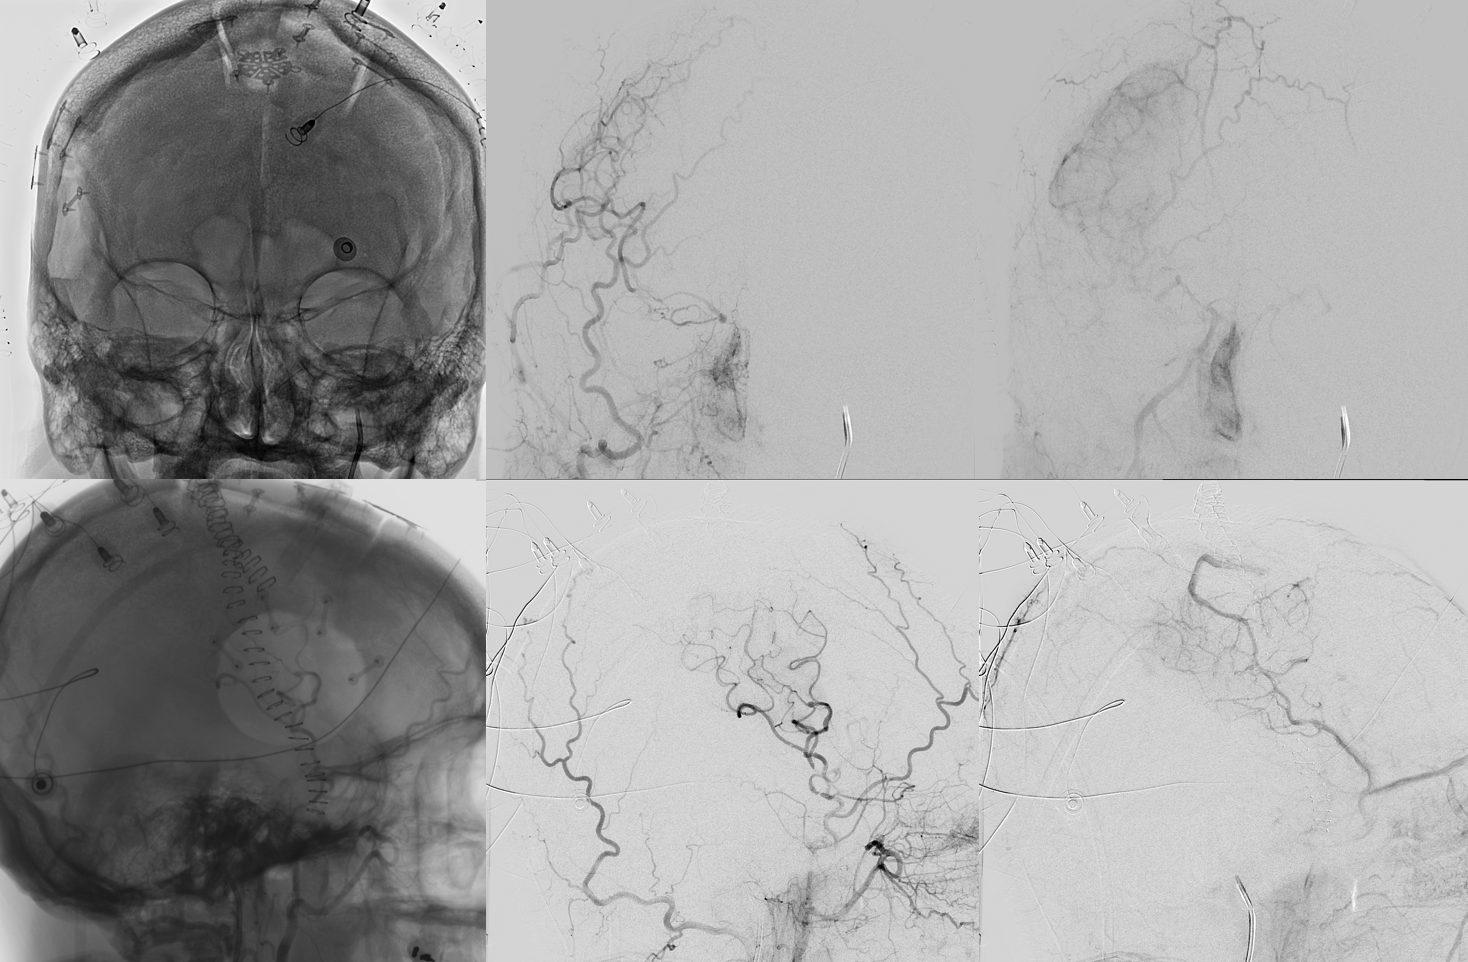

Angio intraop post bypass- STA-MCA working

ACA-ACA did not have flow at this point. Tested by a left A2 BTO. How does that test for bypass patency?

STA-MCA bypass, right ophthalmic, and right PCOM not enough to supply right ACA at this stage — tested by left supraclinoid bypass — what is the rationale there?